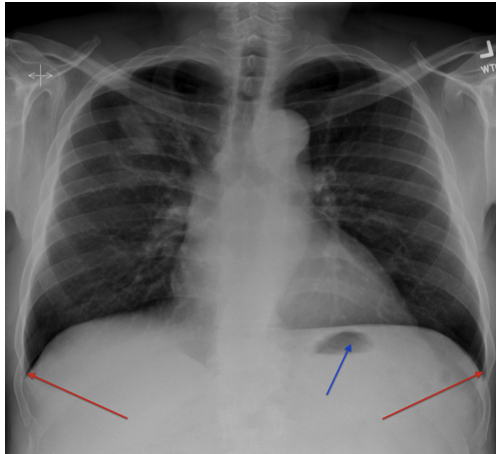

what ribs should you see on a chest xray?

-5-6 anterior ribs (in blue in pic)

-9 posterior ribs (purple)

what condition might be present if there’s more than 6 anterior ribs visible on xray?

-COPD

how to check the diaphragm on chest xray?

-check the position of the R & L semi-diaphragm, the right should be higher than the left due to the liver

-also should be a nice dome shape

-check for any flattening - can be seen in hyper inflated lungs as seen in COPD

-check cardio phrenic and cost phrenic angles on diaphragm

what is a gastric bubble and what does it look like on a chest xray?

-gas in the fundus of the stomach - completely normal

-seen in approx 70% of chest X-rays